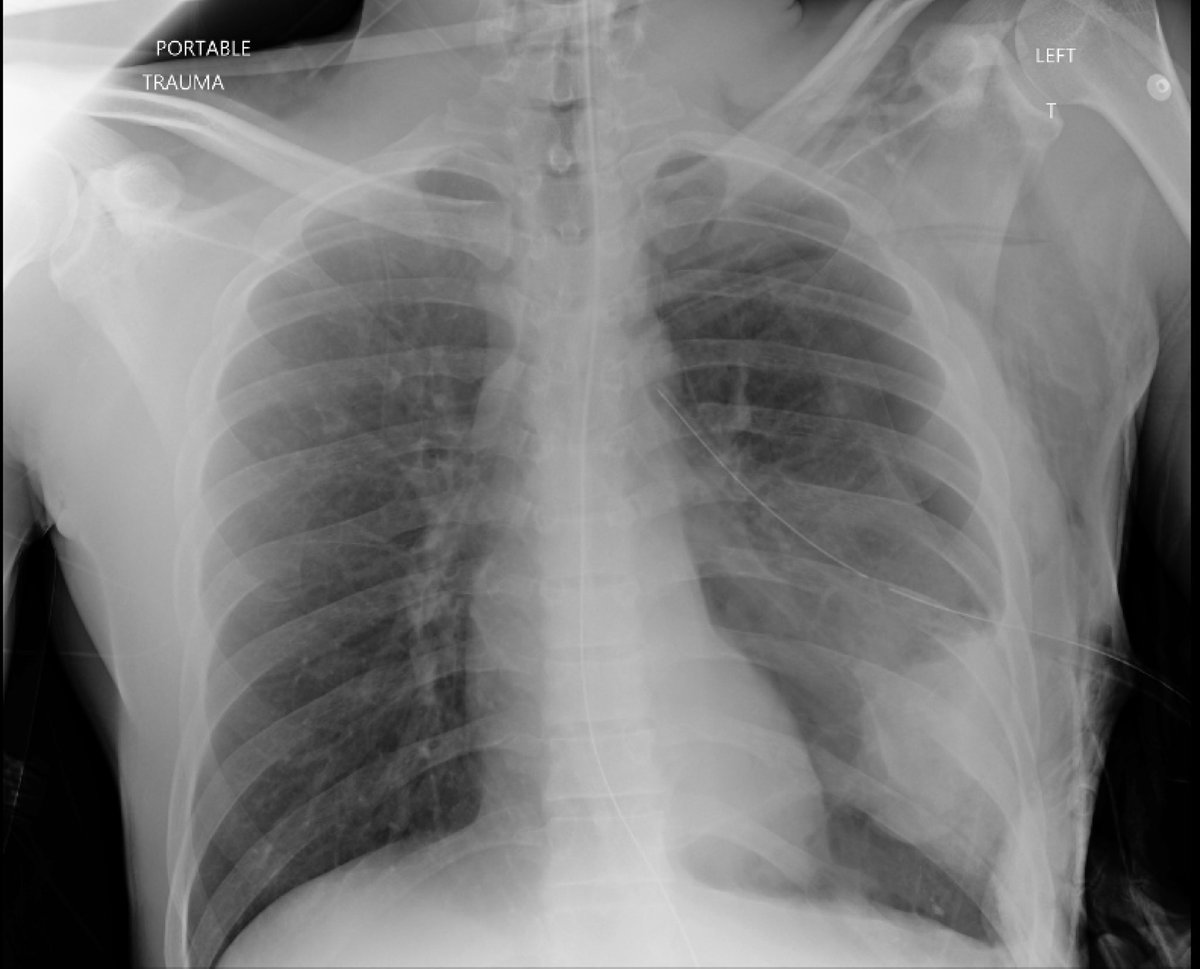

Here’s a Chest X-Ray taken in the ER of a 30-year-old man after being shot in the chest What’s going on here?